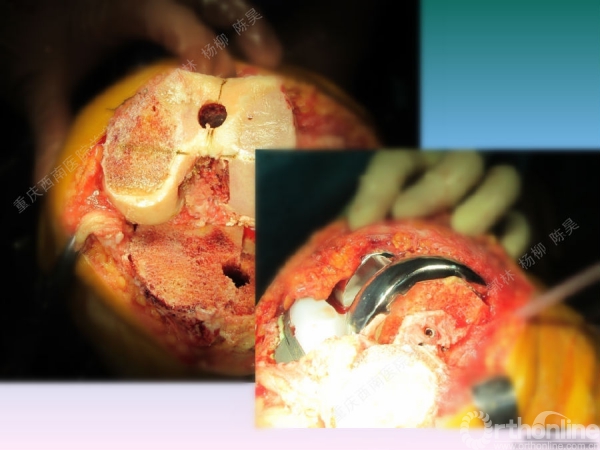

导读:文中,来自重庆西南医院的郭林教授为大家介绍了股骨冠状位关节外畸形的TKA的相关知识,并详细阐述了关节外畸形的概念、诊断、关节内滑移截骨技术等相关内容。

滑移截骨纠正关节外畸形